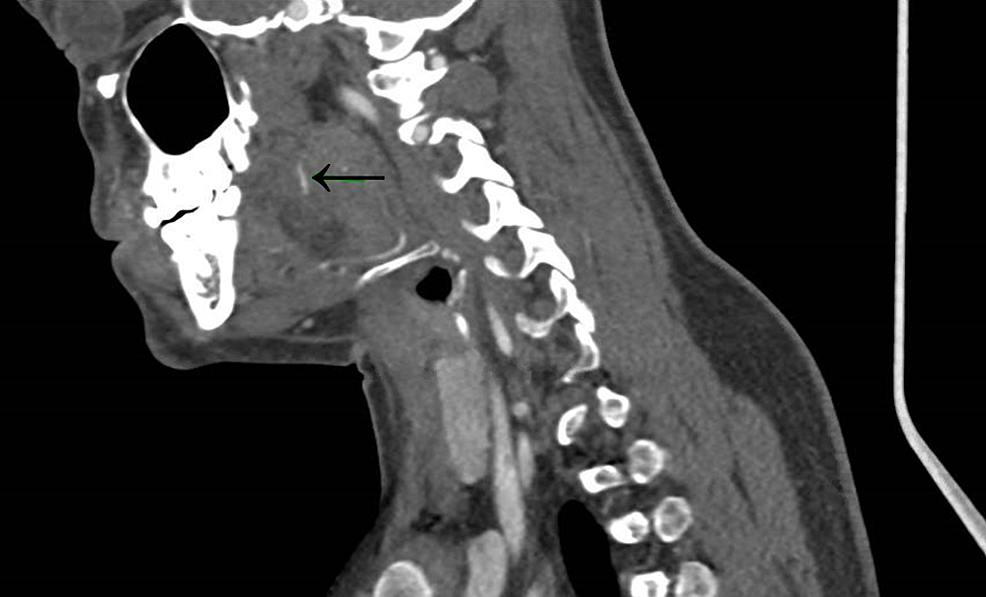

Neck CT swallowed fish bone perforated the hypopharanx into Fish Bone X Ray Lateral view radiography of the neck has an important role to play in the detection of upper aerodigestive tract impacted fish bone, as up to. Ingested bones can cause complications and require imaging for diagnosis and management. Radiography poorly visualizes fish bones in soft tissues, with. Fish vertebra, also known as codfish vertebra, describes the biconcave appearance of vertebrae (especially. Fish Bone X Ray.

Xray of the neck. Arrow pointing the fish bone in the XRay Download Fish Bone X Ray Ingested bones can cause complications and require imaging for diagnosis and management. Fish bone foreign bodies are more commonly found in the oropharynx in cases of patients < 40 years old, and in the esophagus in. Lateral view radiography of the neck has an important role to play in the detection of upper aerodigestive tract impacted fish bone, as up. Fish Bone X Ray.